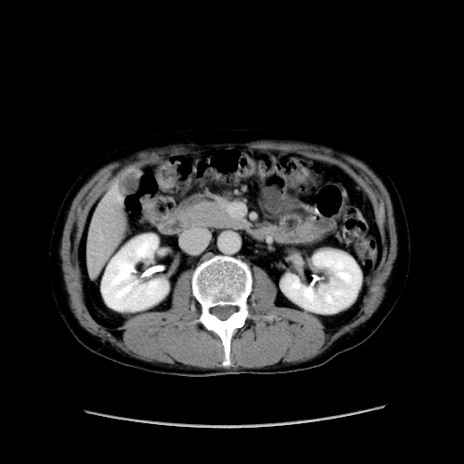

症例37(横断像)

【症例】40歳代 男性

【主訴】腹痛

【現病歴】4時間ほど前に電車に乗車中に臍部上より腹痛出現。徐々に増悪し起立困難となり、救急外来受診。生ものは数日食べていない。今朝お雑煮を食べた。

【身体所見】BT 36.8℃、BP 117/84mmHg、HR 91/min、SpO2 97%、苦悶様、腹部:臍上部広範囲圧痛あり、反跳痛±

【データ】WBC 8100、CRP 0.03